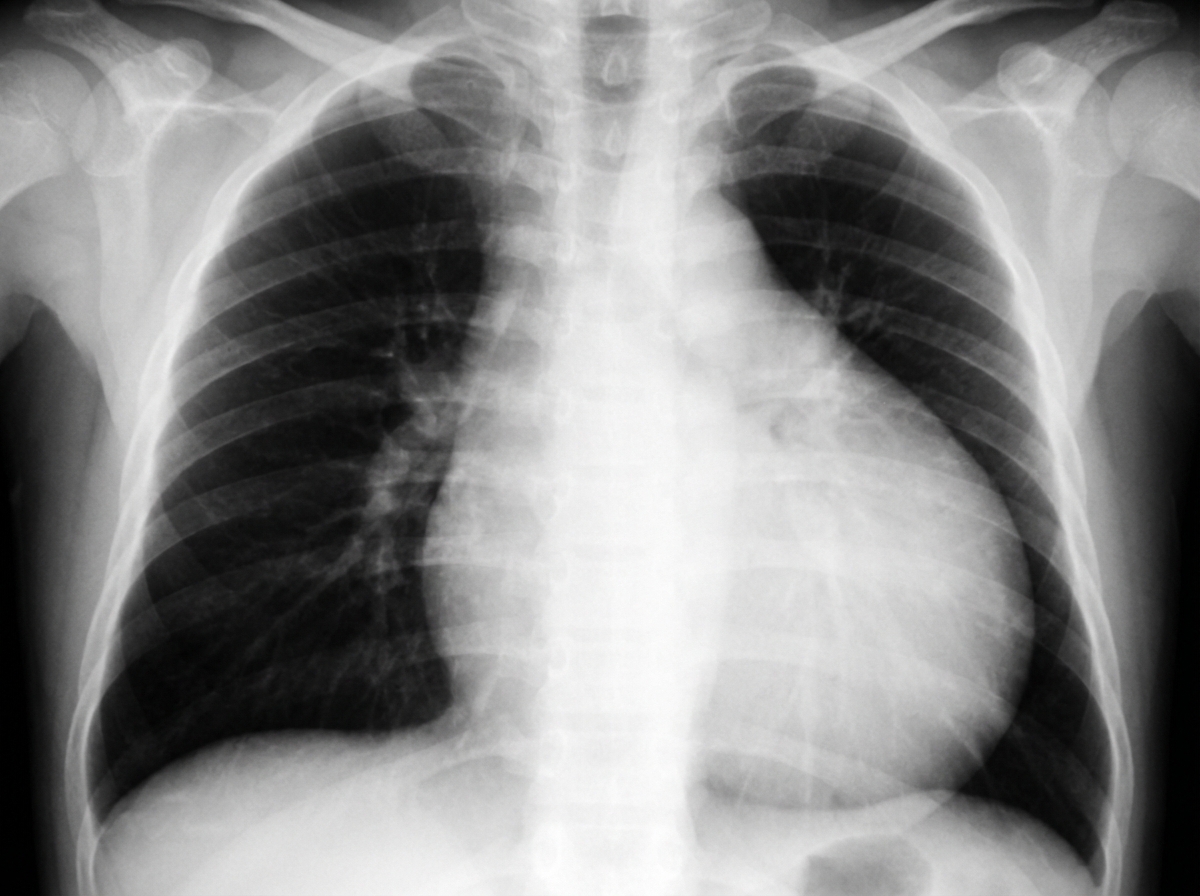

A 27-year-old woman, primigravida, gave birth to a boy 3 months ago and now presents the newborn to your clinic for evaluation. She did not receive prenatal care. She reports that she was taking a medication for her mood swings, but cannot remember the medication’s name. The baby was born cyanotic, with a congenital malformation of the heart that is characterized by apical displacement of the septa and posterior tricuspid valve leaflets. A chest radiograph is shown in the image. Which of the following medications was the mother most likely taking?